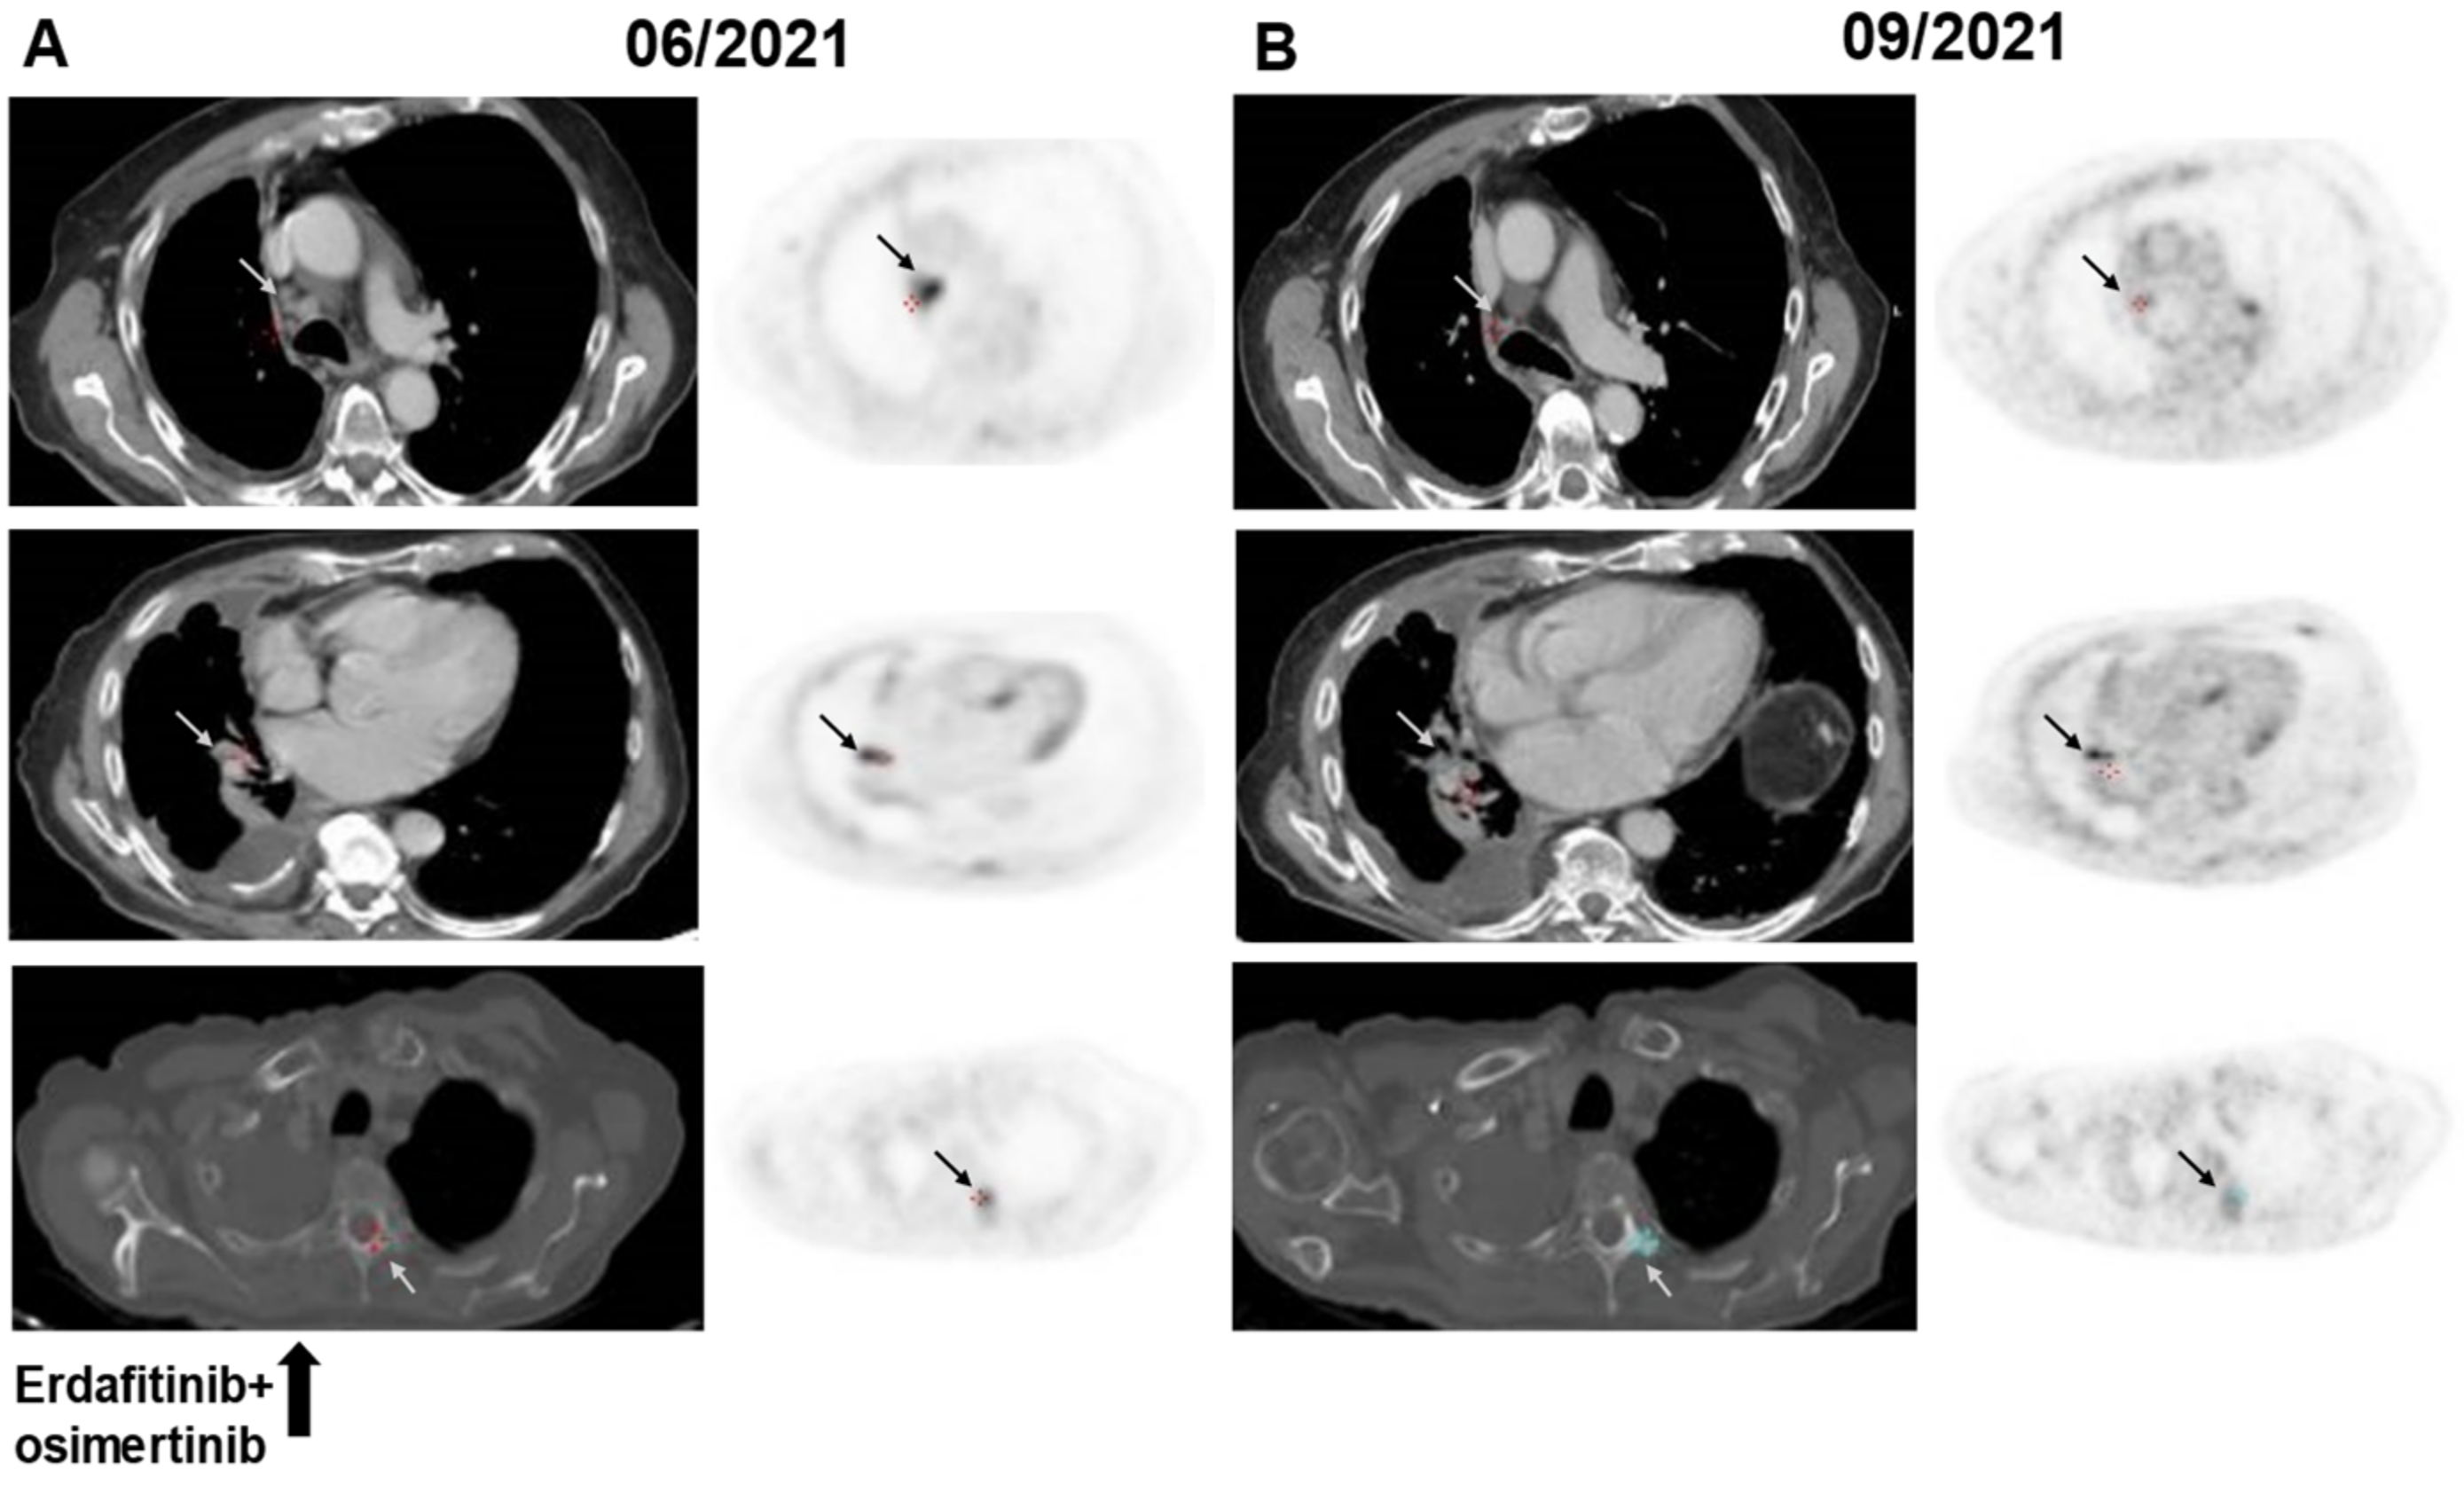

| #3 | F | 63 | ADC | Never- smoker | L747_A750delinsP | Gefitinib (52 mo), osimertinib (14 mo) | 0.07 | Gardant360: EGFR L747_A750delinsP, 0.5, PIK3CA V344G, 1.3 Tempus xT: EGFR L747_A750delinsP, 14.4, EGFR p. C797S, 3.6, PIK3CA V344G, 15.9 |